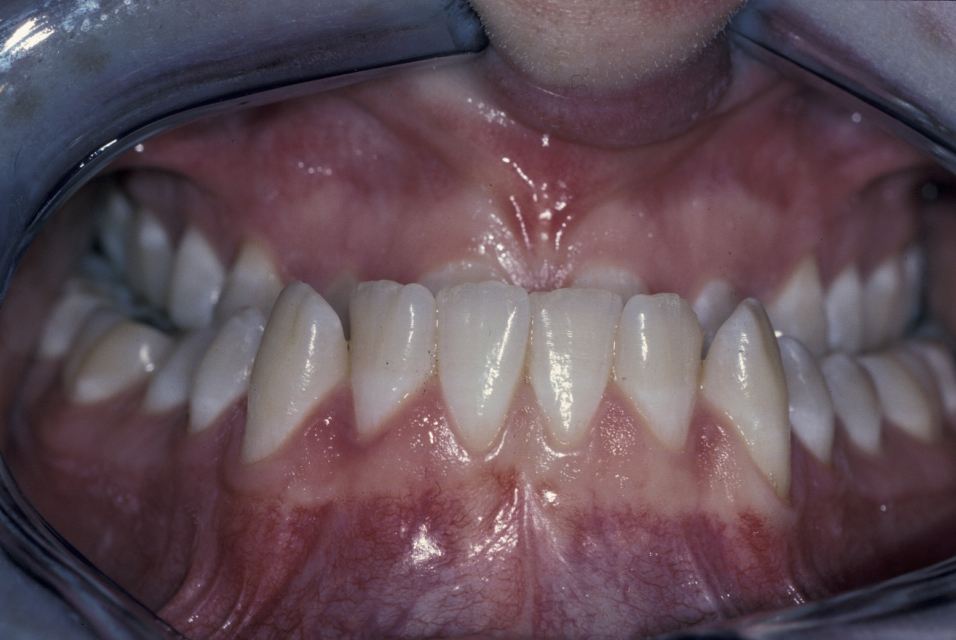

The molar and incisal relationships are examined visually and are formally documented by photographs (see Figure 5, Figure 6 and Figure 7 for examples) and study models (see below).

Figure 5: Intraoral view showing a class III malocclusion (underbite).

Figure 6: Intraoral view showing a class III malocclusion (underbite).

Figure 7: Intraoral view of a class III malocclusion (underbite).

It is essential that both the patient and the orthodontic and surgical team are clear about this phase because orthodontic decompensation prior to surgery will make the occlusal relationships significantly worse. The presurgical orthodontic phase can last between 12 and 18 months (Figure 16).

Figure 16: Intraoral view of a patient with a class II malocclusion who is undergoing orthodontic treatment.